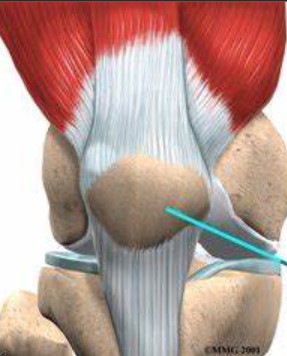

- 当运动员撕裂前交叉韧带时,膝盖在旋转或突然改变方向时容易弯曲。为了恢复膝关节的稳定性,医生可能会建议进行前交叉韧带重建,在受损的前交叉韧带的位置插入一条新的韧带。双束前交叉韧带重建是一种较新的技术,已经被开发出来,为了能够更好地达到正常前交叉韧带的功能。.....

- 很多人都知道前交叉韧带(ACL)撕裂时,会听到膝盖处“砰“的一声响。但殊不知相当一部分的情况实际上是发生髌骨脱位。这类损伤的疼痛程度并不亚于ACL撕裂,毫无疑问,髌骨脱位也需要进行紧急处理,并需确定运动员重放赛场的最佳机会。可以说,髌骨脱位发生率可能远超人们的想象! .....

- 膝关节前交叉韧带损伤的发生率逐步增加,在膝关节韧带损伤中居首位。膝关节前交叉韧带损伤后导致膝关节不稳定可引起半月板损伤和退行性关节炎等继发损伤,严重影响患者日常生活和运动功能。目前,很多学者认为膝关节前交叉韧带损伤关节稳定性的重建,不仅包括生物力学的重建,而且应该有健全的神经肌肉反馈机制的重建。术后.....